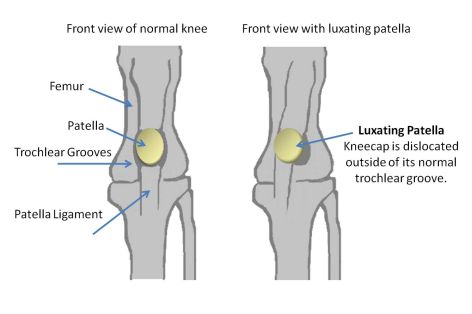

- Aneška MilbaBam - 0/0

- G-Hašlerka Agent Arnak - 0/0

- G-Horalka Agent Arnak - 0/0

- G-Honzík Agent Arnak - 0/0 ( own.: P. Cmíralová )

- Haluška Agent Arnak - 0/1

- Ch. Kosmos Fervidus - 0/0

- Ch.Ml. Jack-A-Dandy Sweet Smile - 0/0

- Naomi Gold Modrý dukát - 0/0

- Tessa Gold Modrý dukát - 0/0

- Ája Agent Arnak - 0/0

- Bee Maya Agent Arnak - 0/0

- Josefínka Agent Arnak 0/0

- Ignác MilbaBam 0/0

- Lojzík MilbaBam 0/0

- Lobelka Agent Arnak 0/0

- Narciska Agent Arnak 0/0

- Nektarinka Agent Arnak 0/0